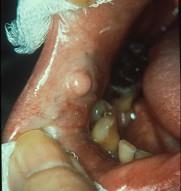

组图为口内纤维瘤的外观,关于此病的描述不正确的是 ( )

组图为口内纤维瘤的外观,关于此病的描述不正确的是 ( )![]()

A生长一般较缓慢

B手术后不易复发

C主要由纤维组织构成

D有可能恶变

E肿瘤边界清楚